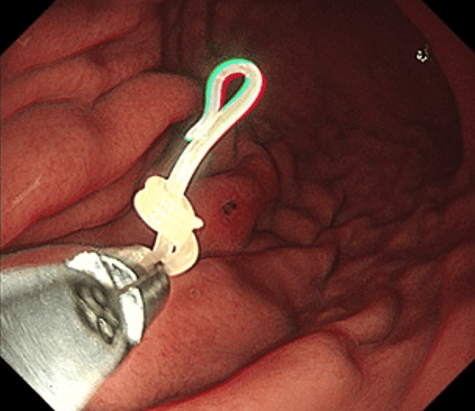

問診で胃アニサキス症が疑われる場合、胃カメラ(胃内視鏡検査)が第一選択となります。内視鏡により胃粘膜に刺入した長さ2~3cmの細長く白い虫体が確認され、それを鉗子で抜去することによって診断・治療を同時に行うことが可能です。

胃アニサキス症治療の第一選択は、胃カメラを用いての虫体摘出です。摘出後はほとんどの場合で、速やかに症状が改善します。

2.鉗子で抜去すると…

6.鉗子で抜去しようとすると…

7.生きているのでよく動きます。TOP